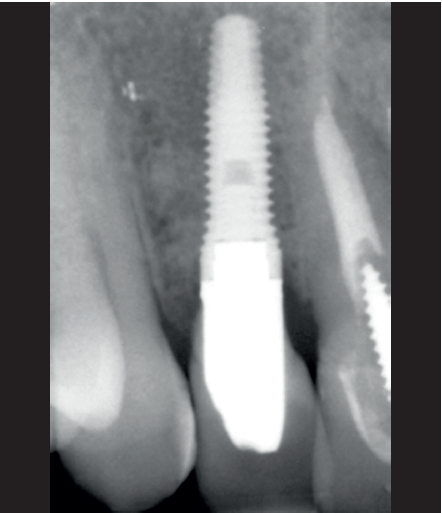

La paciente presenta un provisional removible y el tejido blando circundante a la zona de la emergencia inicial de la prótesis implantosoportada se encuentra en malas condiciones, con una pérdida de grosor importante y los restos de una fístula de tejido blando (Figuras 1-4).

Para continuar con el estudio del caso se realiza un Cone-Beam donde poder observar tridimensional ente la posición del implante situado en posición 1.2. En los cortes seccionales se visualiza completamente situado hacia vestibular con una reabsorción casi completa de la cortical ósea de esta área, lo que explica los problemas de tejido blando subyacente. En la radiografía periapical se observa la posición del implante con respecto a los dientes adyacentes

(Figuras 5 y 6). Con esta imagen se procede a la apertura de un colgajo y la explantación del implante. Se retira también la corona situada en el diente 1.1 para poder realizar otra corona que servirá para apoyar el provisional en extensión para la zona del 1.2, mientras cicatriza la primera intervención. En este primer abordaje se coloca también un injerto en bloque obtenido de la rama mandibular que se fija con un microtornillo en la zona a regenerar donde se ha perdido la cortical vestibular. Una vez fijado y posicionado, se rellena alrededor del injerto en bloque con hueso particulado obtenido con un bone-scraper de la misma zona donante embebido en PRGF-Endoret para una mejor fijación y viabilidad celular (Figuras 7-9).